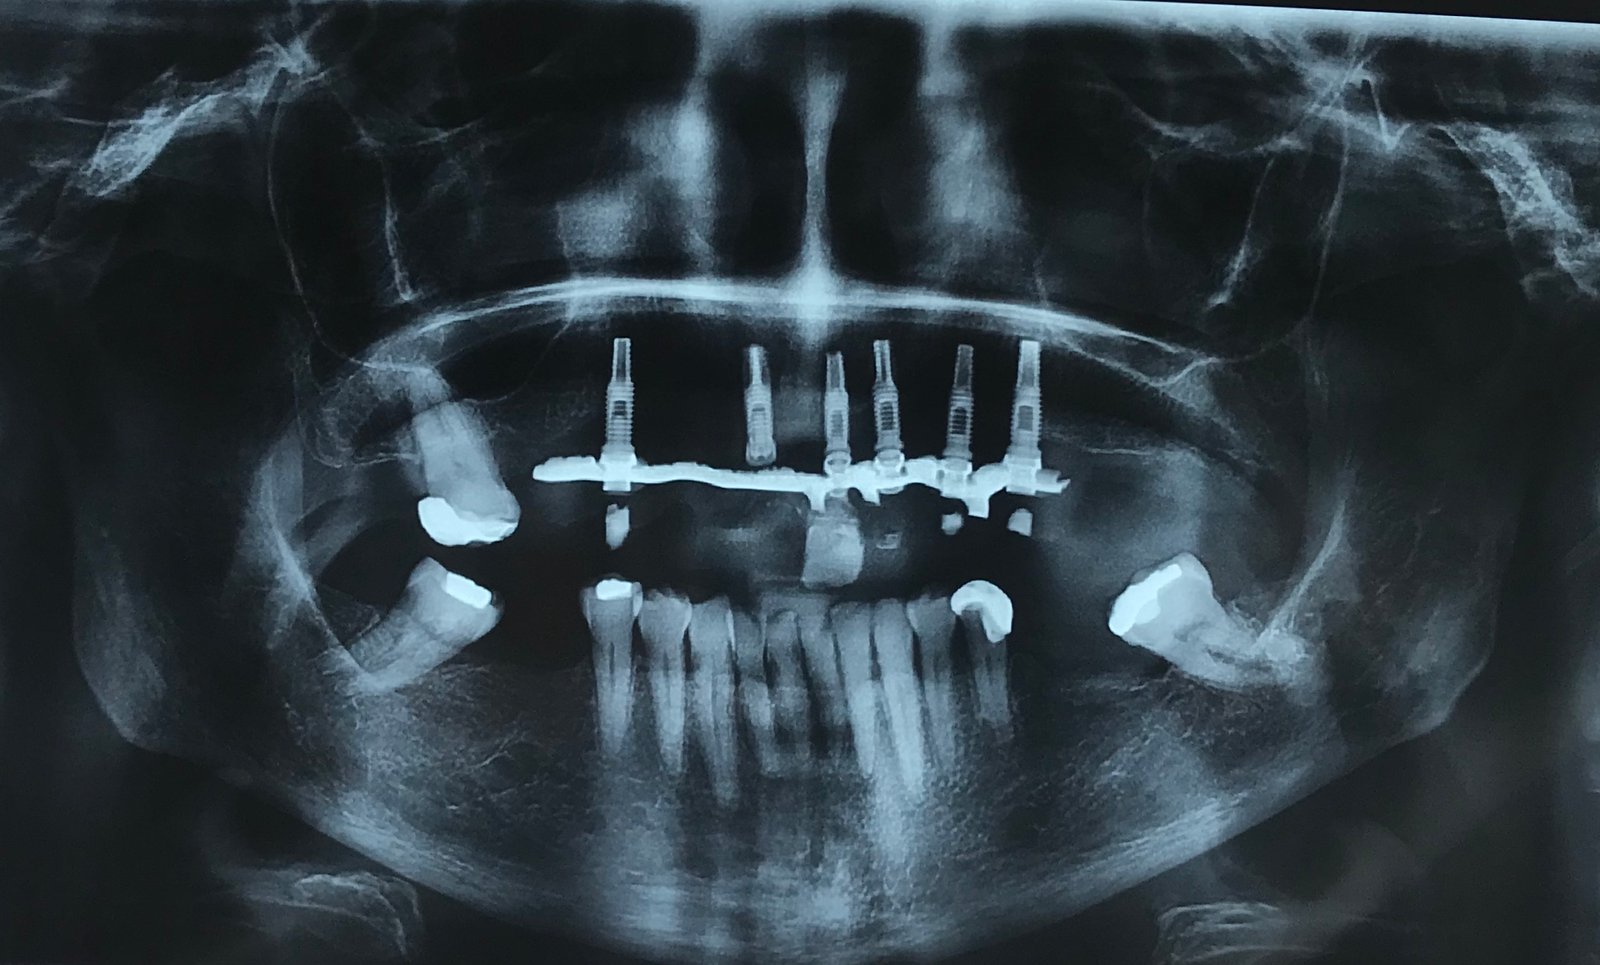

IDENTIFICAR IMPLANTES DEL MAXILAR SUPERIOR

Necesito identificar implantes superiores para cambiar protesis